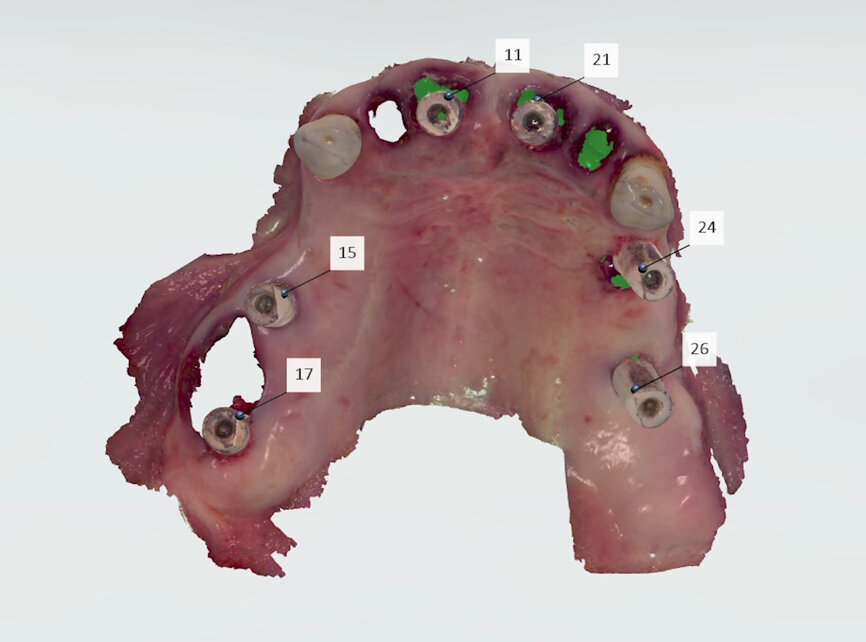

To obtain the final intra-oral surface scan, original Straumann SRA scan bodies were connected to the SRAs under visual control (Fig. 10). A new intra-oral scan was taken to record the patient’s current oral situation, showing the scan bodies and the preserved strategic teeth. This file (File 2) was also sent to the laboratory (Figs. 11 & 12). When the laboratory confirmed receipt of both files, the preserved teeth were extracted and healing caps placed on the abutments, completing the surgery.

On receipt of the scan body file (File 2), the laboratory imported it into 3Shape’s Dental System and created a virtual model, matching the virtual SRA scan bodies from Straumann’s original library with the intra-oral SRA scan bodies (Figs. 13 & 14). A working file was created for designing the temporary prosthetic emergence profile for the SRA.